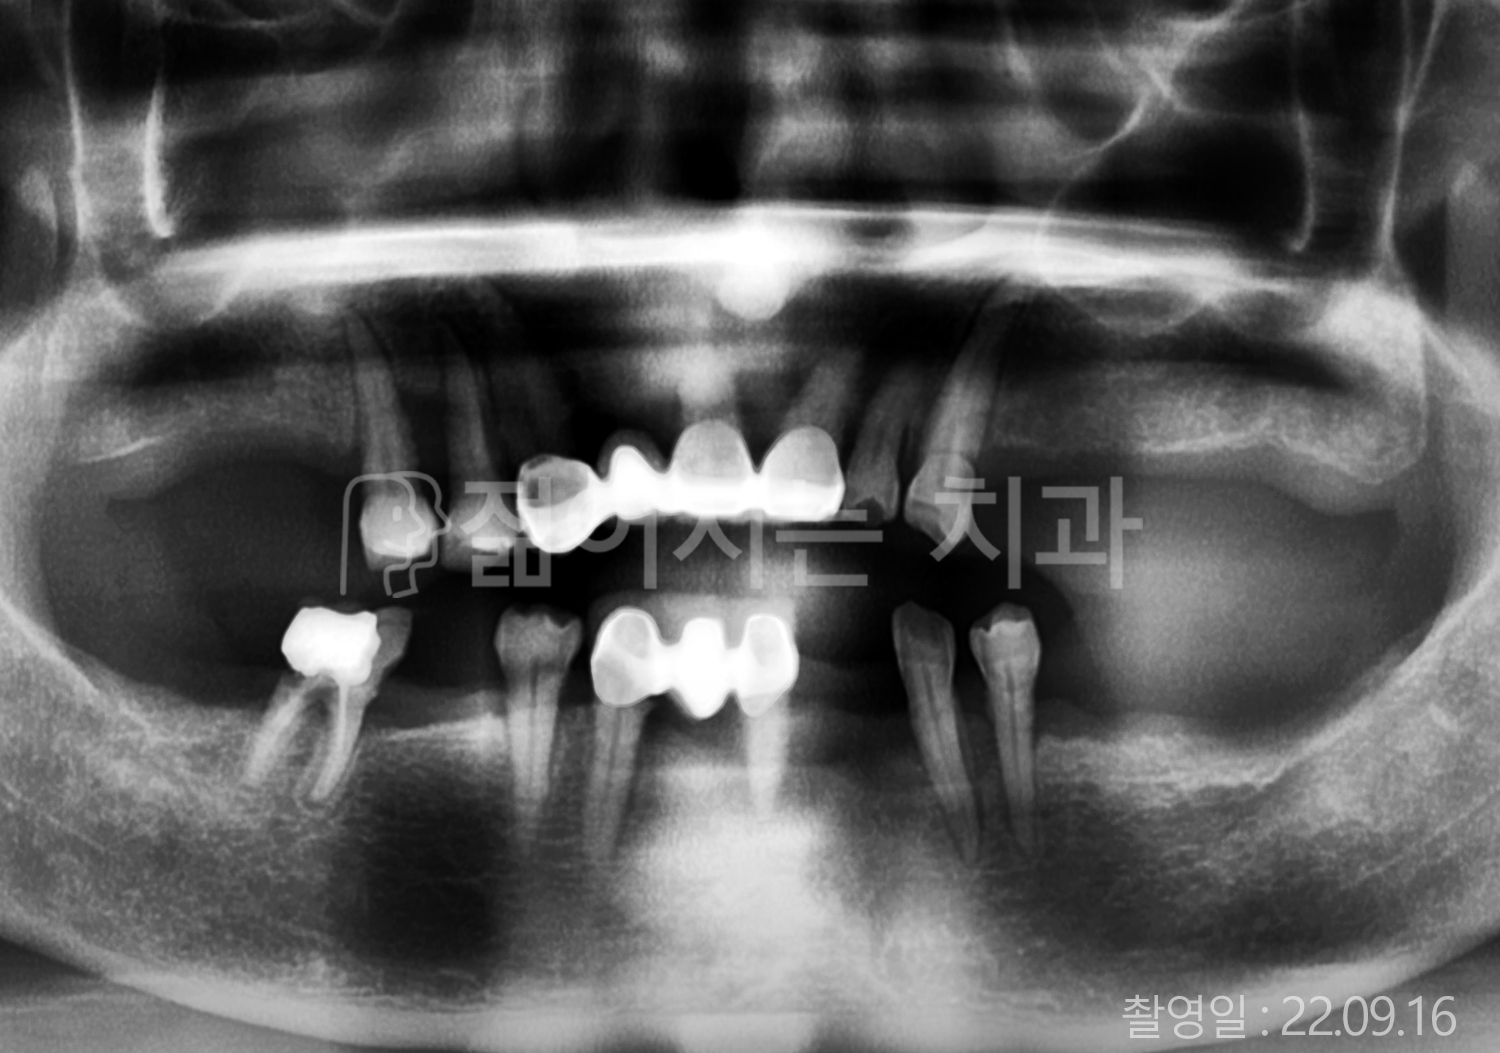

• 60대 고혈압, 고지혈증 전체치아 10개 이상 임플란트

• 70대 전체치아 10개 이상 임플란트

• 60대 전체치아 10개 이상 임플란트

• 50대 전체치아 10개 이상 임플란트

• 50대 고혈압, 고지혈증 전체치아 10개 이상 임플란트

• 60대 고혈압, 당뇨, 고지혈증 전체치아 10개 이상 임플란트

• 80대 고혈압, 당뇨, 골다공증 전체치아 10개 이상 임플란트

• 60대 고혈압 전체치아 10개 이상 임플란트

• 60대 고지혈증 전체치아 10개 이상 임플란트

• 60대 당뇨 전체치아 10개 이상 임플란트